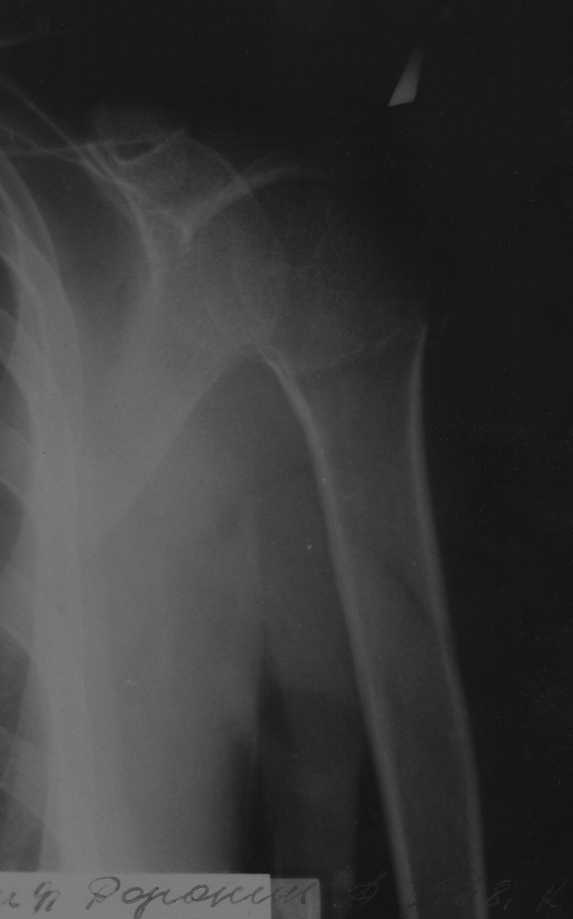

Рентгенологические исследования проксимального отдела плеча состоит из прямого, бокового и аксиальных видов. Если имеются сложные переломы тогда рекомендуется Томография, а так в большинстве случаев достаточно бывает стандартных снимков.

Независимо от условий (нежелание рентгентехника или отсутствие пленок) необходимо добиться рентгенограмм, особенно аксиальной, потому что одна проекция не гарантирует, что не пропущен вывих в плечевом суставе.

На выставленных снимках копии из книги: 1-2 прямая укладка и снимок; 3-3a боковой или Y; 4 аксиальная укладка и снимок.

Для принятия решения и исследования обычно достаточно пару дней, а здесь третья неделя, начало консолидации метафизарной части, надо спешить!